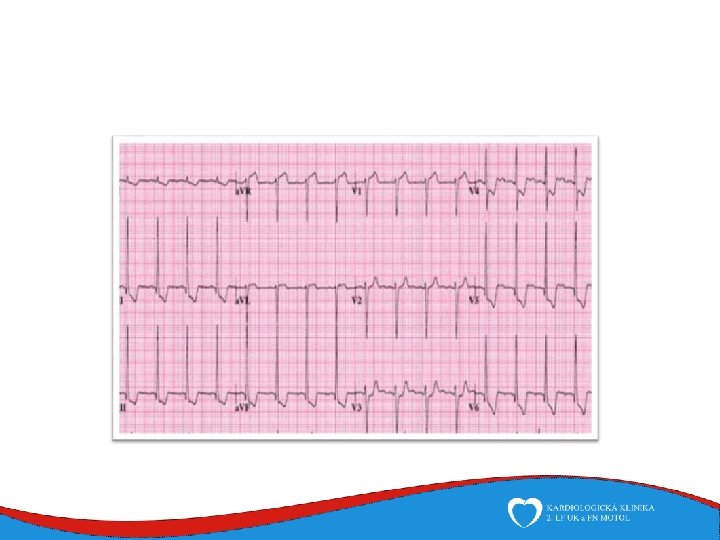

Diagnosis Family history Phisical examination ECG systolic murmur at the apex and lower left sternal border heterogenous LVH, patol. Q , QS, …. ECHO – golden standard MRI septal thickness more than 15 mm, papillary muscles hypertrophy, mitral anterior leaflet elongation, pressure gradient regions of myocarrdial fibrosis regions of late gadolinium enhancement (LGE) Stress test blood pressure responce ECG monitoring ventricular arrhythmia Selective coronarography

Work up ECG – typical - epsilon, neg. T v V 1 -V 3 - LBBB morphology VES ECHO MRI EMB